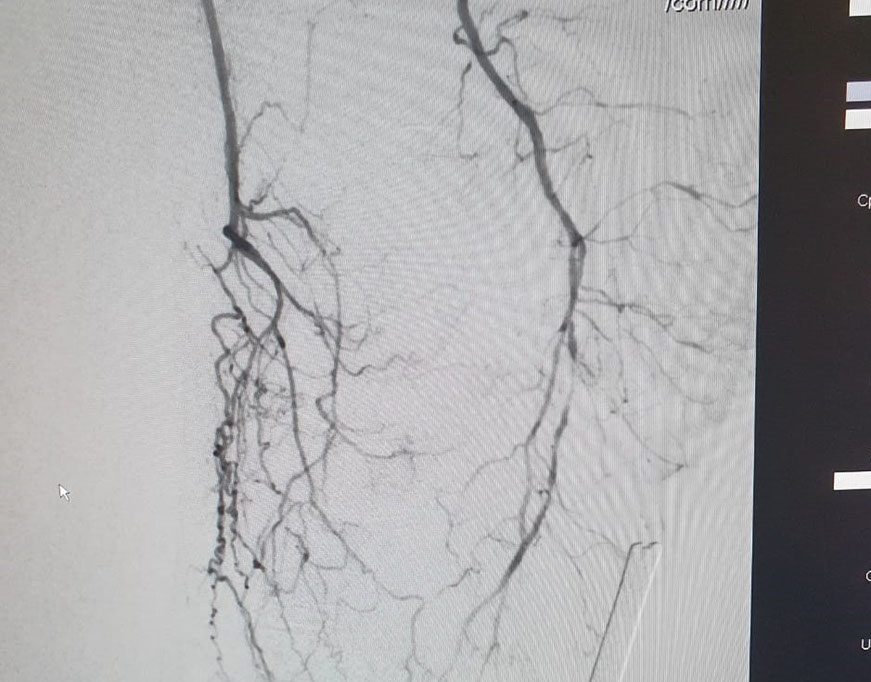

El Dr Sergio Raul Ludueña Jefe del Servicio de Hemodinamia de INCOR nos comentó sobre procedimiento realizado en el día de ayer en en el Servicio. "Queremos compartir con ustedes si bien no es un caso coronario , es un paciente obeso mórbido, diabético, con amputación supracondilea de miembro inferior izquierdo hace 3 años y actualmente con isquemia critica de miembro inferior derecho, con oclusión de ambas tíbiales y sin circulación en el pie".

Se realizó un abordaje híbrido con el Dr. Alejandro Flores, y se re canalizó ambas arterias tíbiales. Procedimiento inédito en nuestra provincia.

Las imágenes siguientes son previas al procedimiento y posterior se ve ambas arterias tíbiales permeables, y circulación en el pie